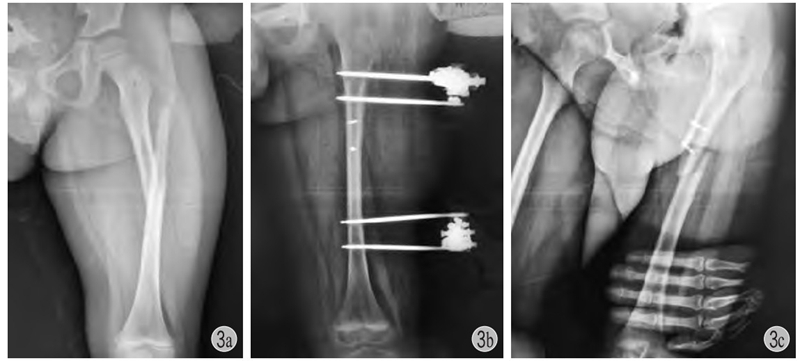

(1)一般来说小年龄患儿的干部骨折不需要切开复位内固定,以股骨干为例,4岁之前通常不用内固定治疗,4~10岁之间通常选用弹性针固定,11岁以上一般考虑青少年锁定髓内钉(图3)。

图3 患儿,男,7岁

a、b:左股骨干骨折,应尽量闭合复位应用弹性针或肌肉下接骨板固定,该患儿切开复位,局部螺钉+外架固定;c:拆除外架后3个月发生再骨折